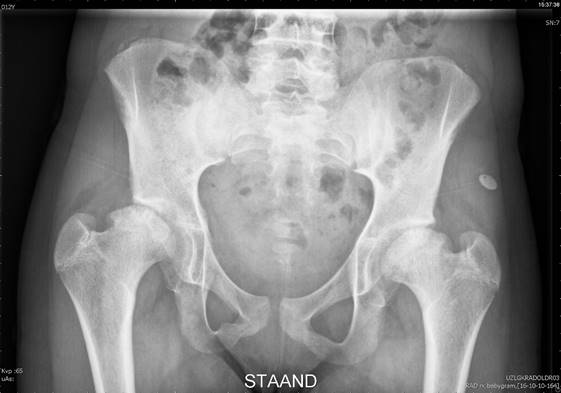

Skeletal survey showed hip dysplasia.